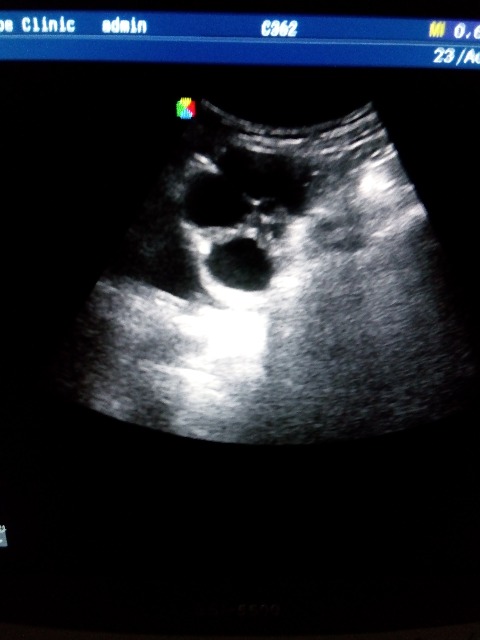

Подскажите что это может быть, лоцируется на уровне дна матки, справа и слева, больше слева, у женщины c-r шейки матки, проходит обследование брюшной полости перед лечением в онкодиспансере, недавно делали УЗИ малого таза, без патологии, никаких образований, кист не находили, жалоб нет. Думаю расширенные петли кишечника, заполненные жидким содержимым, перистальтики не увидела, если это они то какая может быть причина, и как то нужно это в протоколе и заключении отразить?

По фото можно подумать и про яичники и по некоторым фото про петли. Нужно видео!

Форма вытянутая, общей капсулы нет и с двух сторон, наверное кишечник, просто я его таким не видела еще.. ну а если абстрагироваться от этого случая, то что вообще писать в заключении в случае расширенных и заполненных жидкостью петель, если больной амбулаторный планово пришел? какие рекомендации?